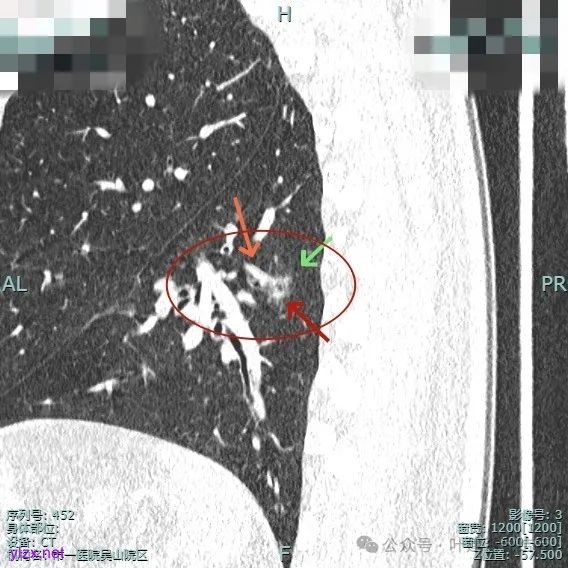

主病灶位于下叶后基底段下肺静脉水平,次病灶在同一层面位靠外基底段交界附近。

薄层上看主病灶不纯,有实性成分,也有血管穿行;次病灶是纯磨,微小的结节,但轮廓与边界较为清楚。

主病灶混合密度,血管进入;次病灶小且淡,但轮廓清。